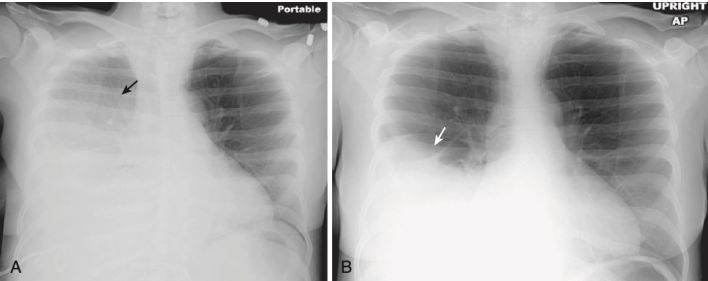

- Ảnh hưởng của tư thế bệnh nhân đến hình ảnh của dịch màng phổi:

- Khi bệnh nhân ở tư thế dựng thẳng, dịch màng phổi chuyển xuống đáy khoang ngực do tác dụng của trọng lực. Khi bệnh nhân ở tư thế nằm ngửa vị trí, dịch tràn di chuyển tự do sẽ tạo lớp dọc theo khoang sau màng phổi và tạo ra một hình ảnh “sương mù” đồng nhất trên toàn bộ nửa ngực khi quan sát từ phía trước (Hình 8).

- Khi bệnh nhân nằm dốc người (tư thế Fowler), dịch màng phổi sẽ tụ lại tạo thành một đậm độ hình tam giác có độ dày khác nhau ở đáy phổi với đỉnh hoặc phần mỏng nhất của tam giác có độ cao khác nhau nhau trong lồng ngực, tùy thuộc vào góc bệnh nhân nằm nâng người và lượng dịch.

- Cạm bẫy: Tùy thuộc vào mức độ góc nghiêng của bệnh nhân, phần trên hai phế trường có thể sáng (đen hơn) nếu bệnh nhân nằm dựng thẳng và chất dịch lắng xuống đáy ngực hoặc tối hơn (trắng hơn) khi bệnh nhân nằm ngả người nhiều hơn và tràn dịch bắt đầu tạo lớp ở phía sau. Sự thay đổi này có thể xảy ra với cùng một thể tích dịch màng phổi do tư thế của bệnh nhân.

- Giải pháp: Tốt nhất là phim chụp X quang phổi di động được chụp với bệnh nhân ở cùng một tư thế.